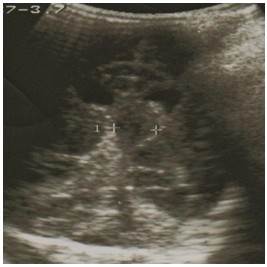

Se decidió realizar control evolutivo mediante ultrasonografía transfontanelar, visualizándose mejoría imagenológica de la lesión descrita. (Figura 4).

Este paciente evolucionó favorablemente bajo observación estrecha y monitoreo ecográfico. Fue descartada la posibilidad de diátesis hemorrágica7 por tan buena evolución y exámenes de laboratorio normales.